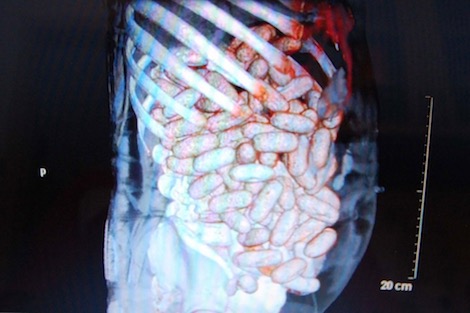

علم لدى منطقة أمن مطار محمد الخامس الدولي، أن الكمية الإجمالية لمخدر الكوكايين التي تم حجزها لدى مواطنة من جنسية برازيلية تبلغ من العمر 23 سنة، بعدما تم تفريغها من أمعائها بالمستشفى الجامعي ابن رشد، اليوم الثلاثاء، بلغت 670 غراما من مسحوق الكوكايين. وأفاد بلاغ للمديرية العامة للأمن الوطني أن عناصر الشرطة بمطار محمد الخامس الدولي بمدينة الدار البيضاء، كانت قد أوقفت المشتبه فيها يوم 25 يناير الجاري، وذلك أثناء وصولها على متن رحلة جوية قادمة من ساوباولو، بعدما تم الاشتباه في تهريبها للكوكايين داخل أمعائها.

علم لدى منطقة أمن مطار محمد الخامس الدولي، أن الكمية الإجمالية لمخدر الكوكايين التي تم حجزها لدى مواطنة من جنسية برازيلية تبلغ من العمر 23 سنة، بعدما تم تفريغها من أمعائها بالمستشفى الجامعي ابن رشد، اليوم الثلاثاء، بلغت 670 غراما من مسحوق الكوكايين. وأفاد بلاغ للمديرية العامة للأمن الوطني أن عناصر الشرطة بمطار محمد الخامس الدولي بمدينة الدار البيضاء، كانت قد أوقفت المشتبه فيها يوم 25 يناير الجاري، وذلك أثناء وصولها على متن رحلة جوية قادمة من ساوباولو، بعدما تم الاشتباه في تهريبها للكوكايين داخل أمعائها.

وأبرز أنه تم الاحتفاظ بالمشتبه فيها تحت المراقبة الطبية بالمستشفى الجامعي ابن رشد بغرض استخراج الكبسولات من أمعائها، والتي أسفرت في النهاية عن حجز كمية مخدر الكوكايين على شكل 57 كبسولة.

الصورة من الارشيف